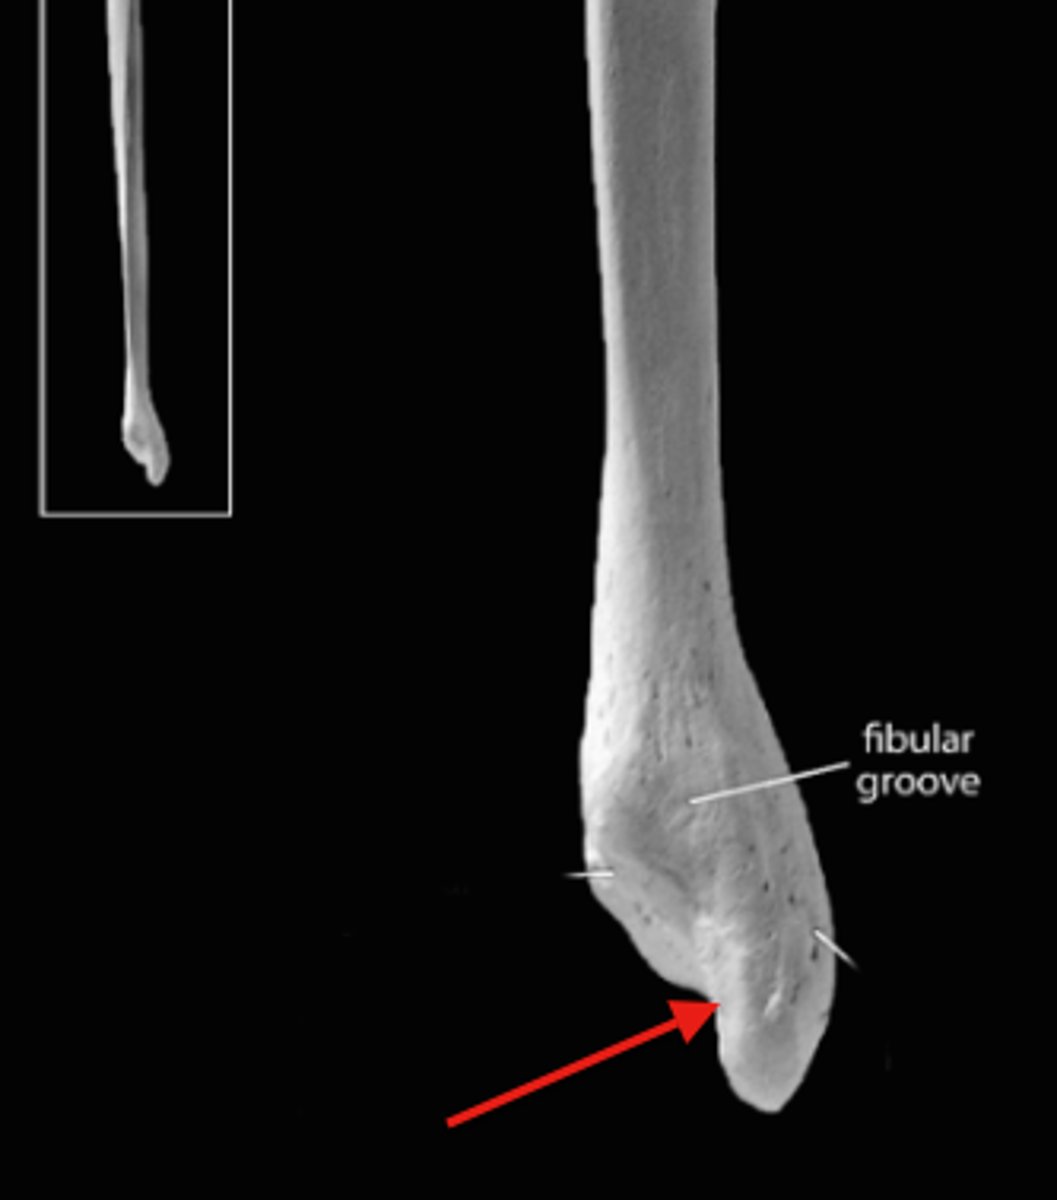

malleolar fossa of fibula

what is this bony landmark called?

right

if the malleolar fossa indentation on the fibula faces towards you what side of the body is that bone from?